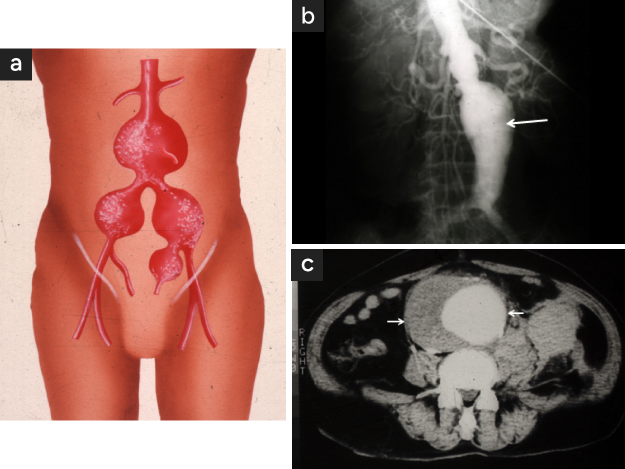

大動脈瘤は、大きくなっても無症状で経過することが多く、患者さんが自覚することはほとんどありません。通常は、X線撮影やCT検査などで偶然発見されることが多いです〈図1 a,b,c〉。

直径3cm以上は腹部大動脈瘤と定義され、腎動脈下腹部大動脈に好発します〈図1 a,b,c〉。動脈瘤は年間に約0.5cmずつ拡大していきます。瘤径が4cmを超えると、1年以内に破裂する危険性が約15%に達するため、一般的に4〜5cmを手術の適応としています。〈図2〉。

図1

図1. 腹部大動脈瘤

• 腹部大動脈〜腸骨動脈瘤の模式図

• 腹部大動脈瘤(矢印)の大動脈造影像

• 腹部大動脈瘤(矢印間)の CT 画像